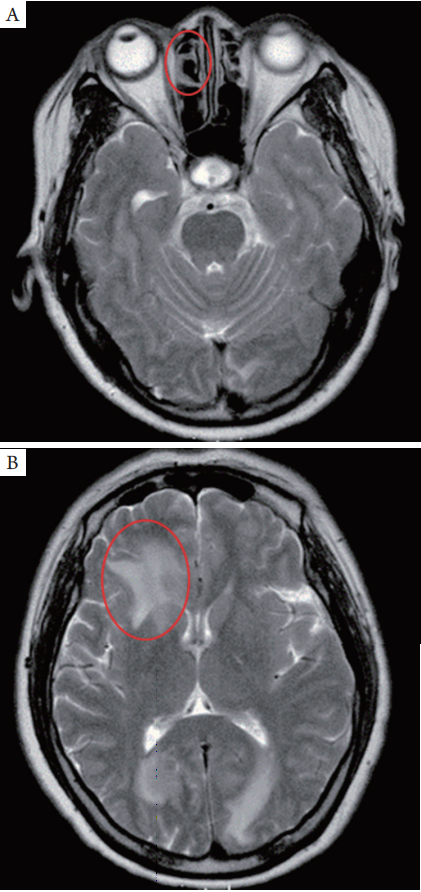

患者就诊时视力右眼0.1 (20 / 200) ,左眼1.0(20/20),眼压右眼50 mmHg,左眼15 mmHg。右眼结膜中度充血,角膜轻度水肿,瞳孔收缩伴虹膜后粘连(图1A)。玻璃体中度混浊,大面积脉络膜脱离,眼底窥不清。超声生物显微镜(ultrasound biomicroscopy,UBM)提示前房角关闭(图1B)。左眼角膜、前房、瞳孔均未见明显异常,晶体轻混(图1C),眼底后极部(图2A)及颞侧周边(图2B)散在多灶性网膜下黄色斑点,上方网膜周边部可见大片黄橘色的网膜下渗出,周边多个小的浸润灶(图2C)。FA荧光血管造影中期可见轻度渗漏与视网膜色素上皮(retinal pigment epithelium,RPE)颗粒样改变(图2D),上方网膜周边可见大面积低荧光区域、RPE层可见多处高荧光(图2E),与眼底镜下所见网膜下黄色病灶相符。ICG晚期可见相应病变区域呈弱荧光(图2F)。光学相干断层扫描(optic coherence tomography,OCT)显示光感受器内节/外节(inner/outer segments,IS/OS)层与RPE/ Bruch膜复合体轻度不规则(图3)。继续予抗炎与抗青光眼治疗,双眼状况仍未有改善。2016年6月,右眼视力降为光感,对患者行右眼诊断性玻璃体切除术,玻璃体标本的细胞学检查结果发现非典型性大淋巴样细胞(图4)。患者头颅MRI轴位T2加 权像(T2W)提示右侧筛窦扩大、增厚(图5A),鼻窦活检确诊为DLBCL来源。MRI还提示右侧胼胝体存在脑部病变(图5B)。患者左眼自始至终未出现症状。因患者PVRL并发PCNSL,目前正在接受局部与全身化疗。

图5 PVRL患者头颅MRI

(A)轴位T2加权像(T2W)低平面扫描可见右侧筛窦扩大、变形、壁增厚(红圈所示);(B)T2W可见右侧胼胝体局灶性高密度影(红圈所示)。